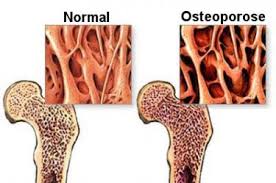

Dia Mundial e Nacional da Osteoporose: Conheça os mitos e verdades sobre a doença

Médico esclarece dúvidas sobre o problema que atinge 10 milhões de pessoas no Brasil Celebrado em 20 de outubro, o Dia Mundial e...